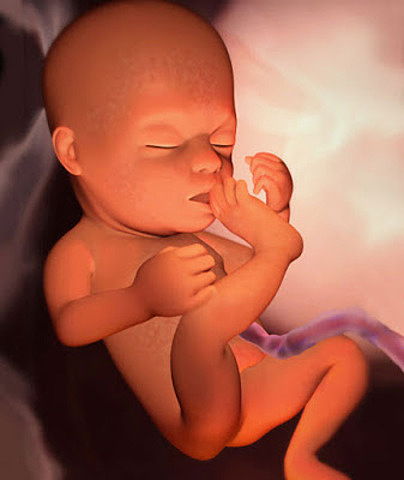

• Semana 14

Semana 14

A las 14 semanas de embarazo pesará unos 30 gramos y medirá aproximadamente 10 centímetros. Parece un bebé en miniatura.

Sus rasgos faciales van haciéndose cada vez más evidentes y hasta podríamos ver como hace gestos con los músculos de su cara, se chupa el dedo y la manita.